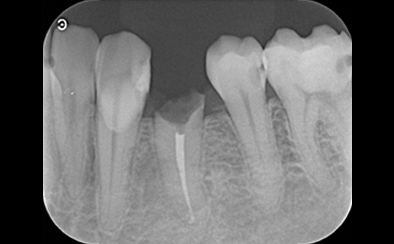

治療前

治療後

写真の白丸部分に膿が溜まっていて痛みと腫れがあり、半年も続いているそうです。これを治療した歯科医師はこれで治らなかったら抜歯してインプラント治療という選択をしました。

歯の状況や、顎骨の状況、また、患者さんご自身からもできるだけ自分の歯を残したいというご希望だったので、精密根管治療を天然歯の保存を目的として計画しました。

まず、根管内のガッタパーチャ(根管充填材)を除去、さらにマイクロスコープによる拡大視野とラバーダム防湿法により丁寧に汚れを除去しました。根管内の感染源がなくなったことを確認したうえで、通常のガッタパーチャとシーラーでは緊密な根管充填ができないと診断し、患者さんに説明したうえでMTA (ProRoot MTA)を選択しました。

3回の治療を行った後、痛みと腫れ、また上の画像にあった丸印の膿の袋もなくなっています。ということは、インプラントせずにこの上にクラウンを被せて治療を終了することができます。

| 費用 | コア除去:22,000円 根管治療:132,000円 MTA根管充填:33,000円 合計:209,000円 |

| リスク・副作用 | 治療中に一時的な咬合痛や冷温水痛、若干の歯肉の腫れ、発赤などを生じることがあります。また仮歯の時期には仮歯の脱離や破損の可能性、舌感などに違和感を覚えることがありますが、本歯に移行するまでに通常消失します。 ※すべて症例による違いや個人差があります。 |

※表示金額は全て税込みです。